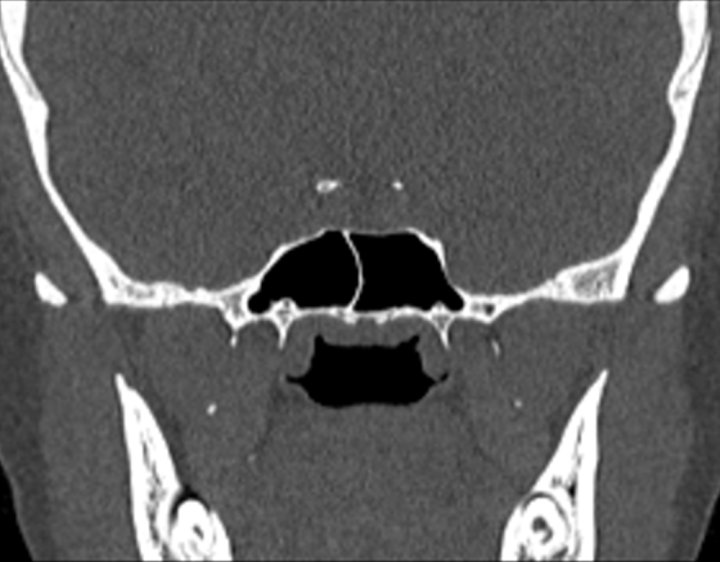

Click any image for labels.